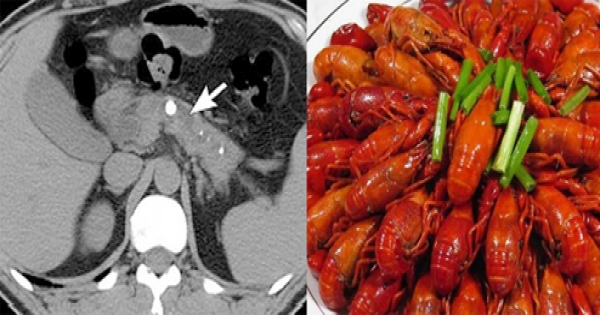

眼下正是小龍蝦大量上市季節,家住湖北省武漢市江岸區百步亭社區的余先生為了嘗鮮,一次吃下3盆小龍蝦,結果劇烈腹痛被緊急送醫。在醫院抽出大半管乳白色的油脂,被診斷為急性重症胰腺炎,險些丟命!

CT檢查發現,他的胰腺有滲出壞死,且血脂高出正常值近30倍,醫生抽血竟然抽出大半管油脂,診斷他患了脂源性重症急性胰腺炎,且胰頭已經壞死,有生命危險。

隨後,醫生為余先生做手術,清除了壞死的胰腺組織,事後,余先生脫離危險住院進一步治療。